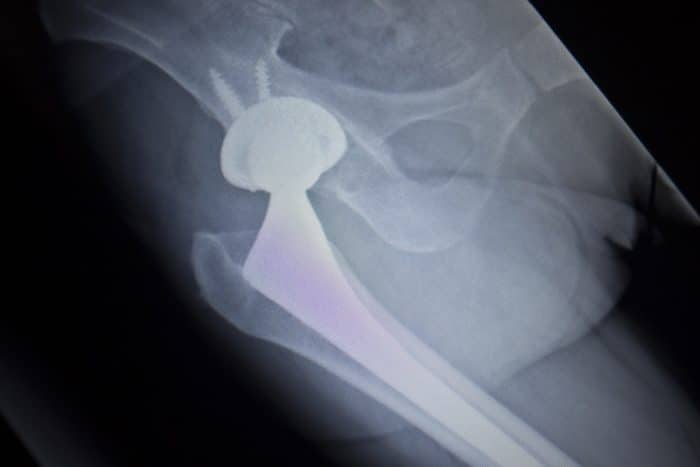

A hip replacement is done to correct a problem with the bones and joint of the hip-part of the bone and joint is removed and is replaced with a synthetic…

Stryker hip implants are artificial joints that are designed to resemble a normal, healthy joint. Designed for those people who are experiencing debilitating pain in the hip, which cannot be…